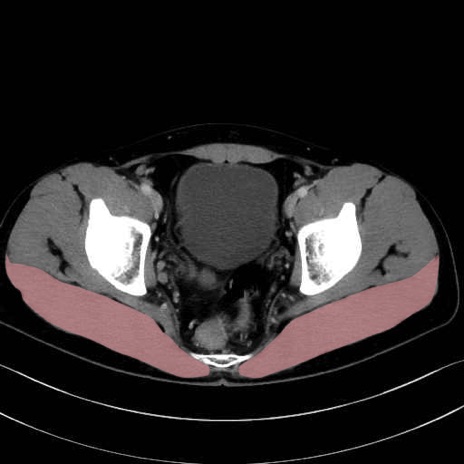

大殿筋 (Gluteus maximus)